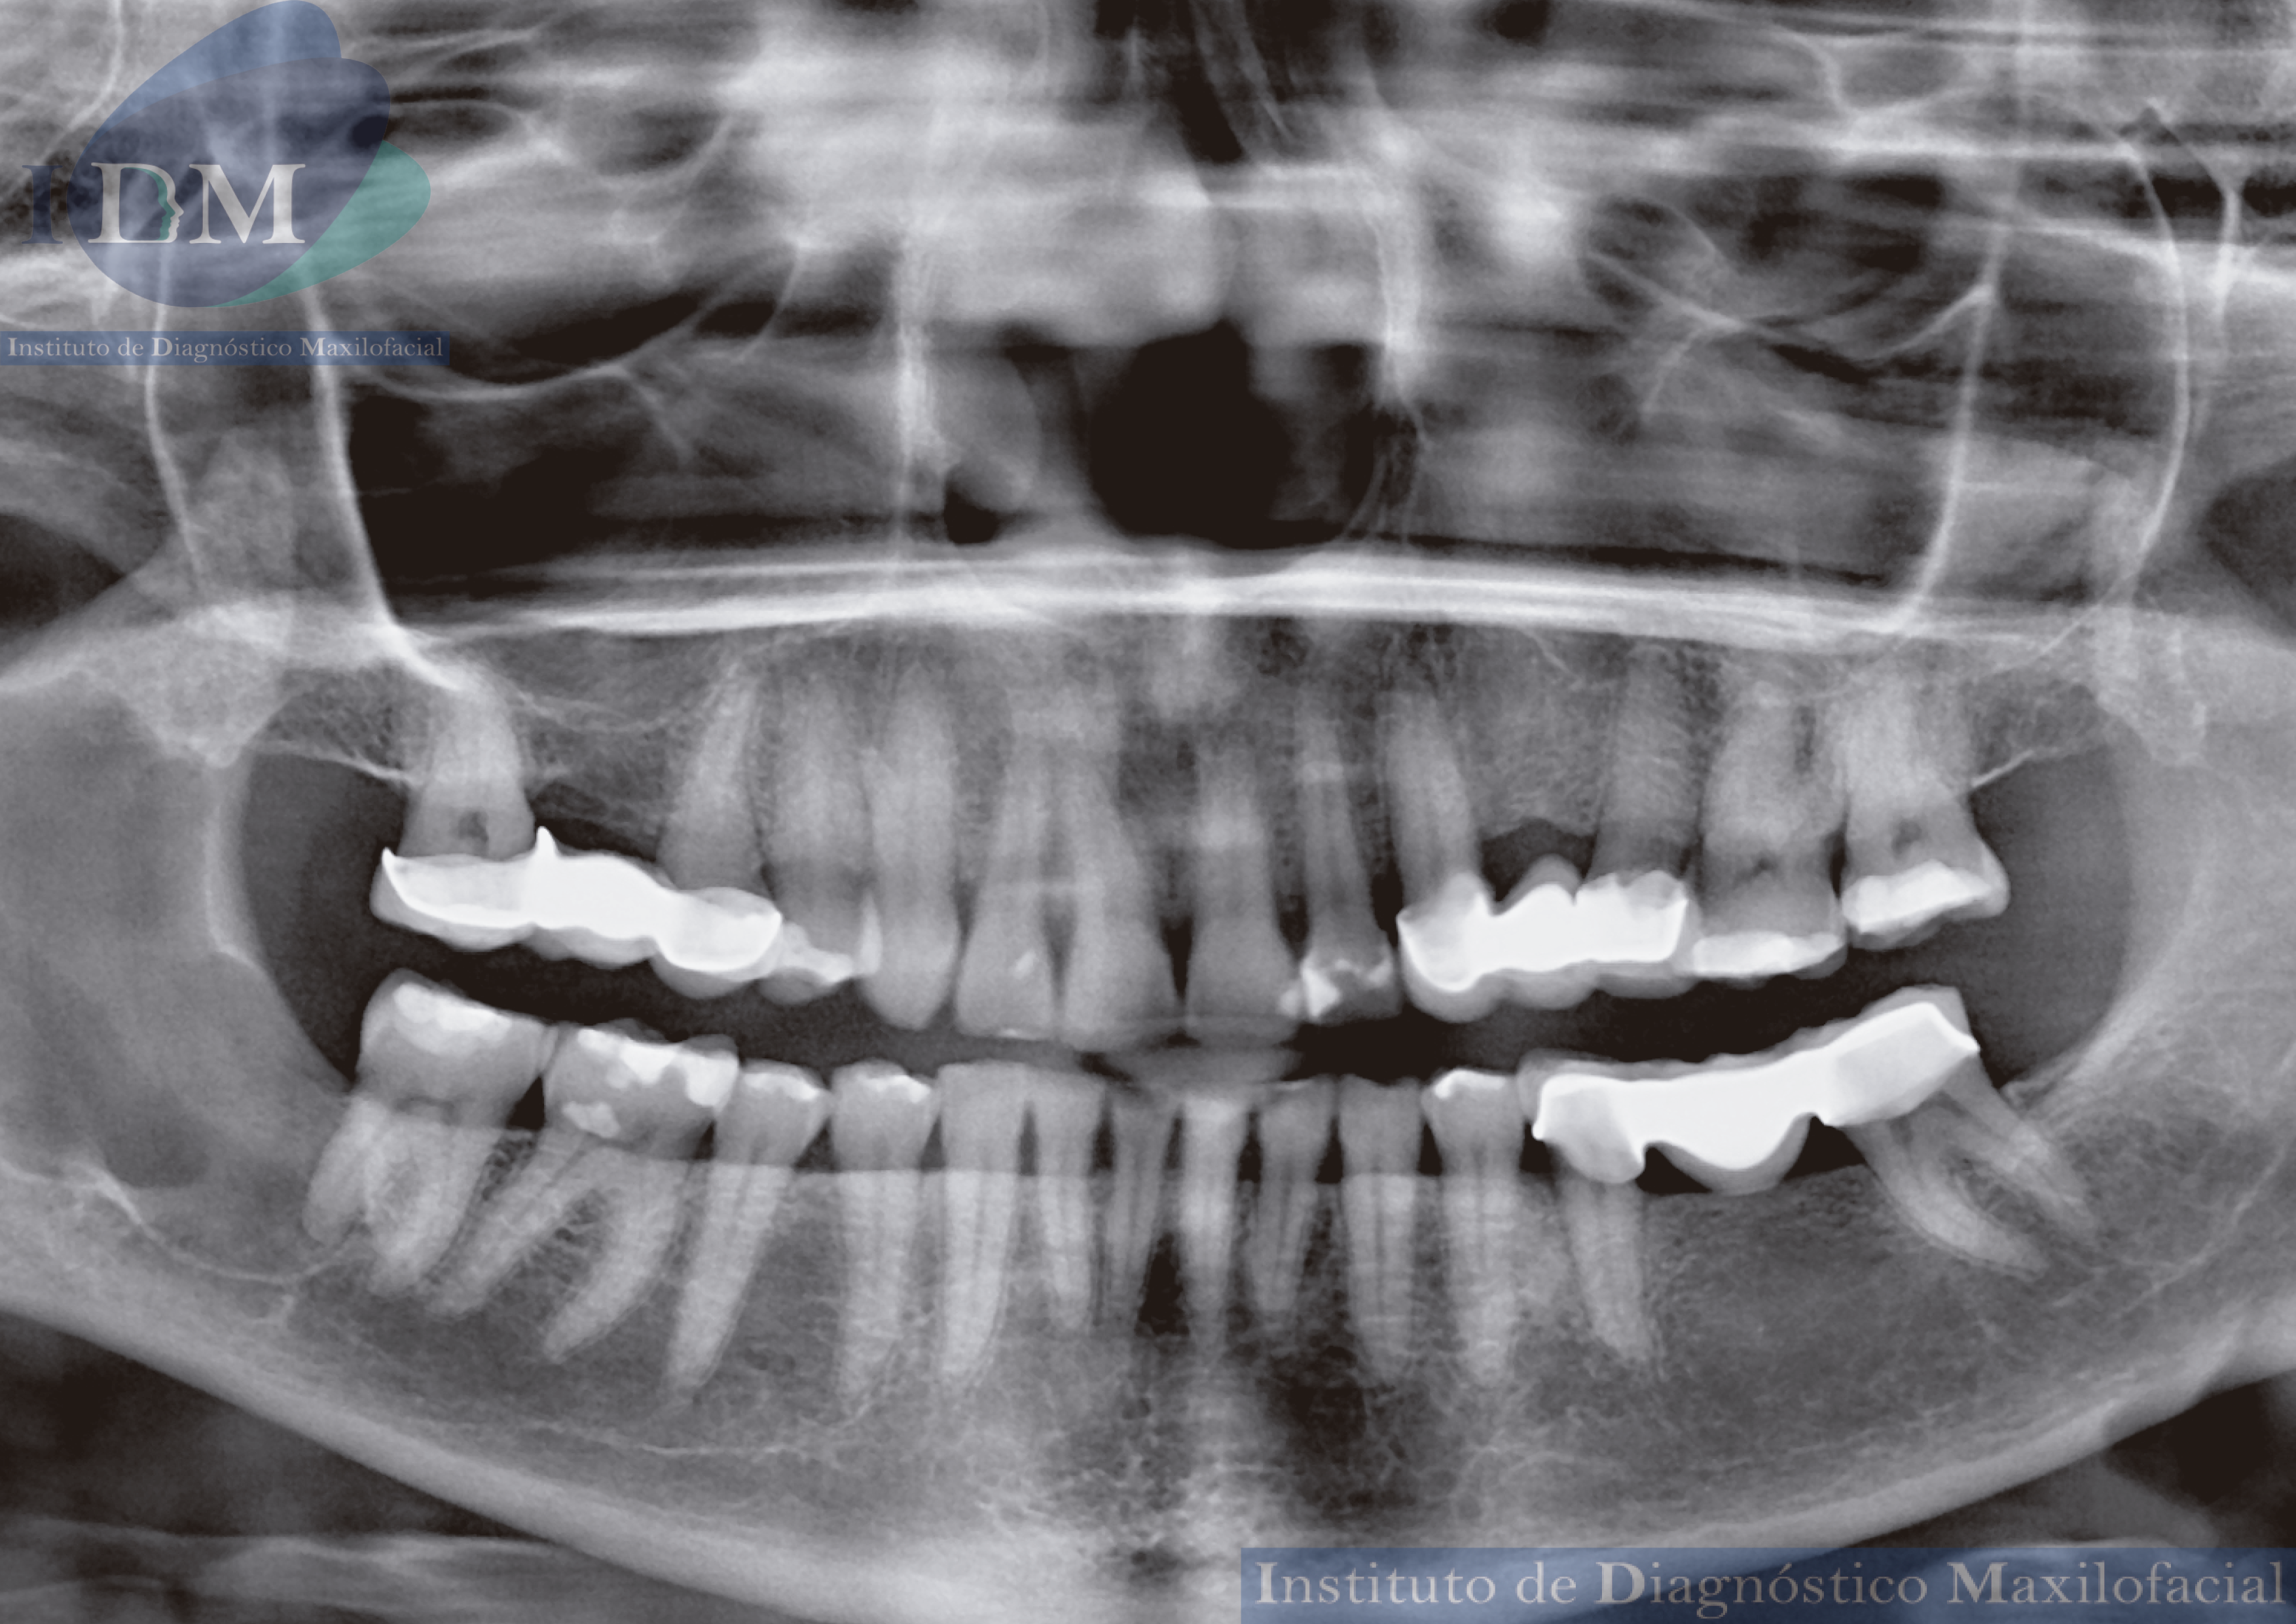

Paciente femenino de 57 años acude al Instituto de diagnóstico maxilofacial (Sede Jesús María) para la evaluación del maxilar inferior.

Radiografia Panorámica

A la evaluación de la radiografía panorámica se observa una imagen radiopaca corticalizada y de borde definidos en cuerpo y rama mandibular del lado derecho.